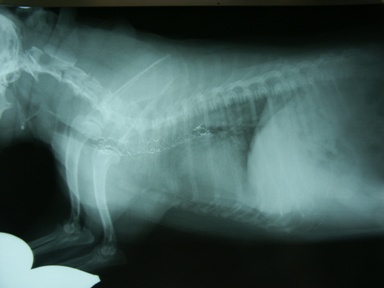

処置:自作シリコンステント(図5)、Wallstentに交換、さらに前方に1本追加(図6)。

図5 症例1の第8病日。自作シリコンステントを頸-胸部気管に留置。